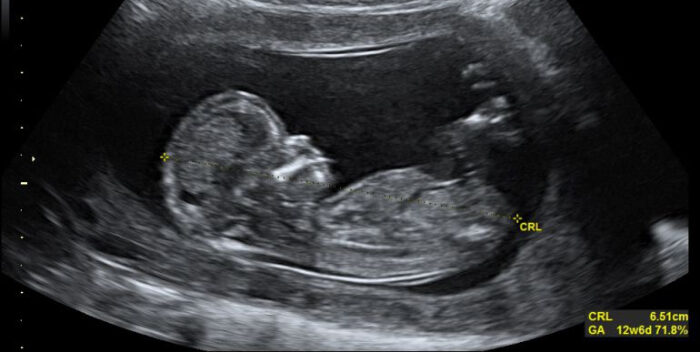

La mujer comienza a entonar una versión en español de “Aleluya”, de Leonard Cohen, y se ve cómo todos los presentes están entusiasmados viendo con dirección a la pantalla, donde aparece el bebé, ya muy bien formado, de perfil.

En un momento, la madre comienza a cantar con más fuerza conforme la canción avanza y la tonalidad aumenta, y la cámara del dispositivo que graba apunta hacia la ecografía, que muestra cómo el bebé parece cantar junto con su madre.

Ante esto, tanto el padre como el técnico del ultrasonido se ven sorprendidos y dicen emocionados “esto es asombroso”, mientras en la pantalla el bebé sigue cantando al ritmo de su madre.